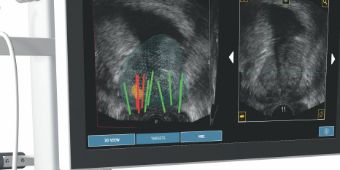

Eine technische Besonderheit des Focal One® besteht darin, dass Bilddateien eines Prostata MRT eingelesen und für die Behandlungsplanung verwendet werden können. In Kooperation mit einem speziell geschulten Radiologen werden sowohl die Umrisse der Prostata, als auch der Tumorareale eingezeichnet. Diese Dateien werden vor der Behandlung in das Computersystem des Focal One® eingespielt.  Focal One® kann anschließend das Ultraschallbild der Prostata und die MRT-Bilder übereinanderlegen („elastische Fusion“), wodurch die gekennzeichneten Tumorareale sichtbar werden.

Auf Grundlage dieser Bilder nimmt der Arzt dann die Behandlungsplanung am Computer vor.  Die Behandlungssonde von Focal One® enthält sowohl einen diagnostischen Ultraschall zur Darstellung der Prostata als auch den Behandlungsultraschall.

Durch eine spezielle Kernspin – Untersuchung der Prostata (multiparametrisches MRT) kann die Lage aggressiver Tumorherde eingegrenzt werden. Eine solche mpMRT Untersuchung kann an verschiedenen auswärtigen Stellen durchgeführt werden, an denen eine Spezialisierung auf mpMRT der Prostata vorliegt. Durch mpMRT/Ultraschallfusion können von diesen Bereichen gezielte Probenentnahme durchführt werden. Dies sog. Fusionsbiopsien führen wir mit dem Koelis Trinity – System durch. Nach Vorliegen aller Befunde kann mit dem Patienten besprochen werden, ob eine fokale Therapie innerhalb eines Studienprotokolls durchgeführt werden kann.